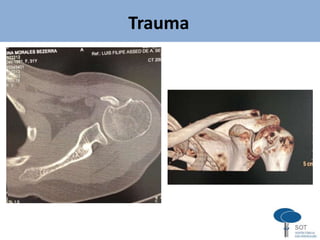

TOMOGRAFIA COMPUTADORIZADA

- Fraturas articulares (head-splitting)

- Fraturas ou fraturas-luxações complexas

- Luxações posteriores

- Fraturas do tubérculo menor